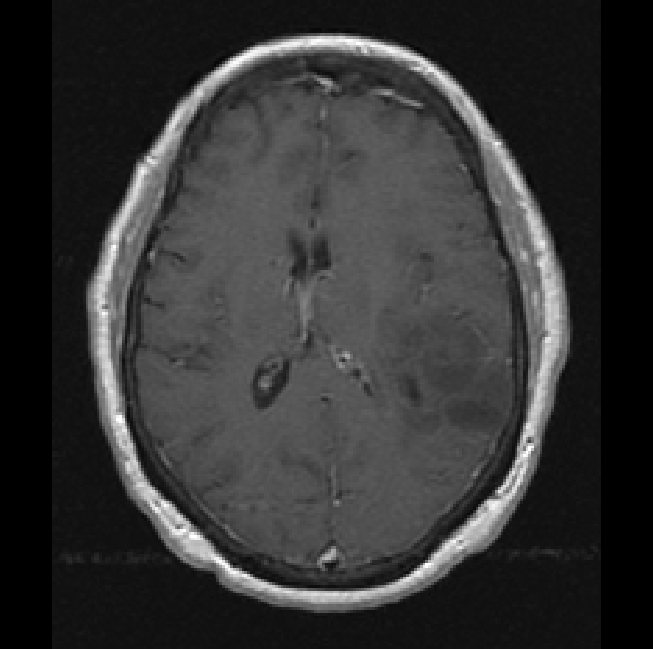

Finally, we considered two examples of scans that were incorrectly predicted by our method, see Figure 9. These two examples were chosen because our network assigned high prediction scores to the wrong classes for these cases. Figure 9(a) shows an example of a grade II, IDH mutated, 1p/19q co-deleted glioma that was predicted as grade IV, IDH wildtype by our method. Our method’s prediction was most likely caused by the hyperintensities in the post-contrast T1w scan being interpreted as contrast enhancement. Since these hyperintensities are also present in the pre-contrast T1w scan they are most likely calcifications, and the radiological appearance of this tumor is indicative of an oligodendroglioma. Figure 9(b) shows an example of a grade IV, IDH wildtype glioma that was predicted as a grade III, IDH mutated glioma by our method.